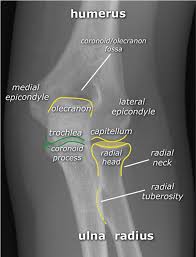

The common extensor tendon attaches to the lateral epicondyle, acting as the common attachment for the superficial extensor muscles of the forearm. The lateral epicondyle of the humerus is a large, tuberculated eminence, curved a little forward, and giving attachment to the radial collateral ligament of the elbow joint, and to a tendon common to the origin of the supinator and some of the extensor muscles. Tennis elbow assessment explore the. Related online courses on physioplus. Lateral epicondylitis is defined as a pathologic condition of the wrist extensor muscles at their origin on the lateral humeral epicondyle. This area can become tender to the touch. Pain is felt over the lateral epicondyle and radiates down forearm. Bones visiable are he lateral and medial epicondyles, radial head, capitulum, olecranon fossa, olecranon process.

An ununited fracture of the lateral condyle can lead to. The medial and lateral epicondyles are small bony tuberosities on the distal end of the humerus (fig. Lateral elbow is in contact with ir. Tennis elbow assessment online course: Resisted wrist extension with elbow fully extended.

Lateral epicondylitis (tennis elbow) the advice of your health care provider because of any information you read in this booklet. Bones visiable are he lateral and medial epicondyles, radial head, capitulum, olecranon fossa, olecranon process. Pain upon resisted wrist extension. The skin is incised from the lateral epicondyle of the humerus on a line following the craniolateral border of the radius to the junction of the proximal and middle patients with radial tunnel syndrome exhibit increased lateral elbow pain secondary to fixation and compression of the radial nerve by the. Resisted wrist extension with elbow fully extended.